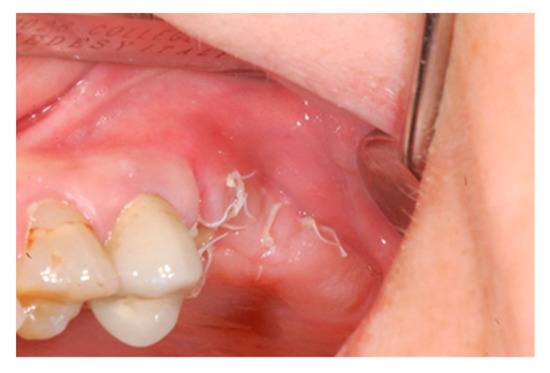

The one-month recall showed a full coverage of the site by epithelialized tissue, thus, indicating perfect healing (Figure 8).

Figure 8.

Intraoperative view of the oral mucosa at one month post tooth extraction. Soft tissues appeared to be completely healed with no signs of bone exposition, considered as a clear sign of BRONJ.